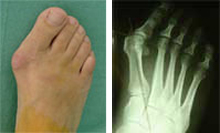

El juanete afecta al 6-10% de la población en general, y es la patología del pie más frecuente, en particular entre las mujeres (20% en la edad adulta y 34% en la tercera edad). Las causas o factores responsables del juanete son diversos: herencia, calzado, forma constitucional del pie y sexo.

- Cirugía del juanete

Todas las técnicas quirúrgicas clásicas se practican a través de la cirugía abierta, que precisa una incisión lateral de 6 cm.

En la actualidad, la cirugía ortopédica con cirugía percutánea permite solventar estas dolencias con rapidez, con dos mínimas incisiones de 3 mm y realizando la intervención con anestesia local y en régimen ambulatorio. Además, la intervención de juanetes se realiza desde la parte interna o lateral y la de las metatarsalgias desde la cara superior del pie, con lo que la herida no incide en la marcha y es posible caminar al salir del quirófano. Precisamente, el apoyo inmediato del pie está aconsejado en el caso de las metatarsalgias para que actúe positivamente en el proceso postoperatorio, ya que recoloca en su lugar de origen las cabezas de los metatarsianos intervenidos.